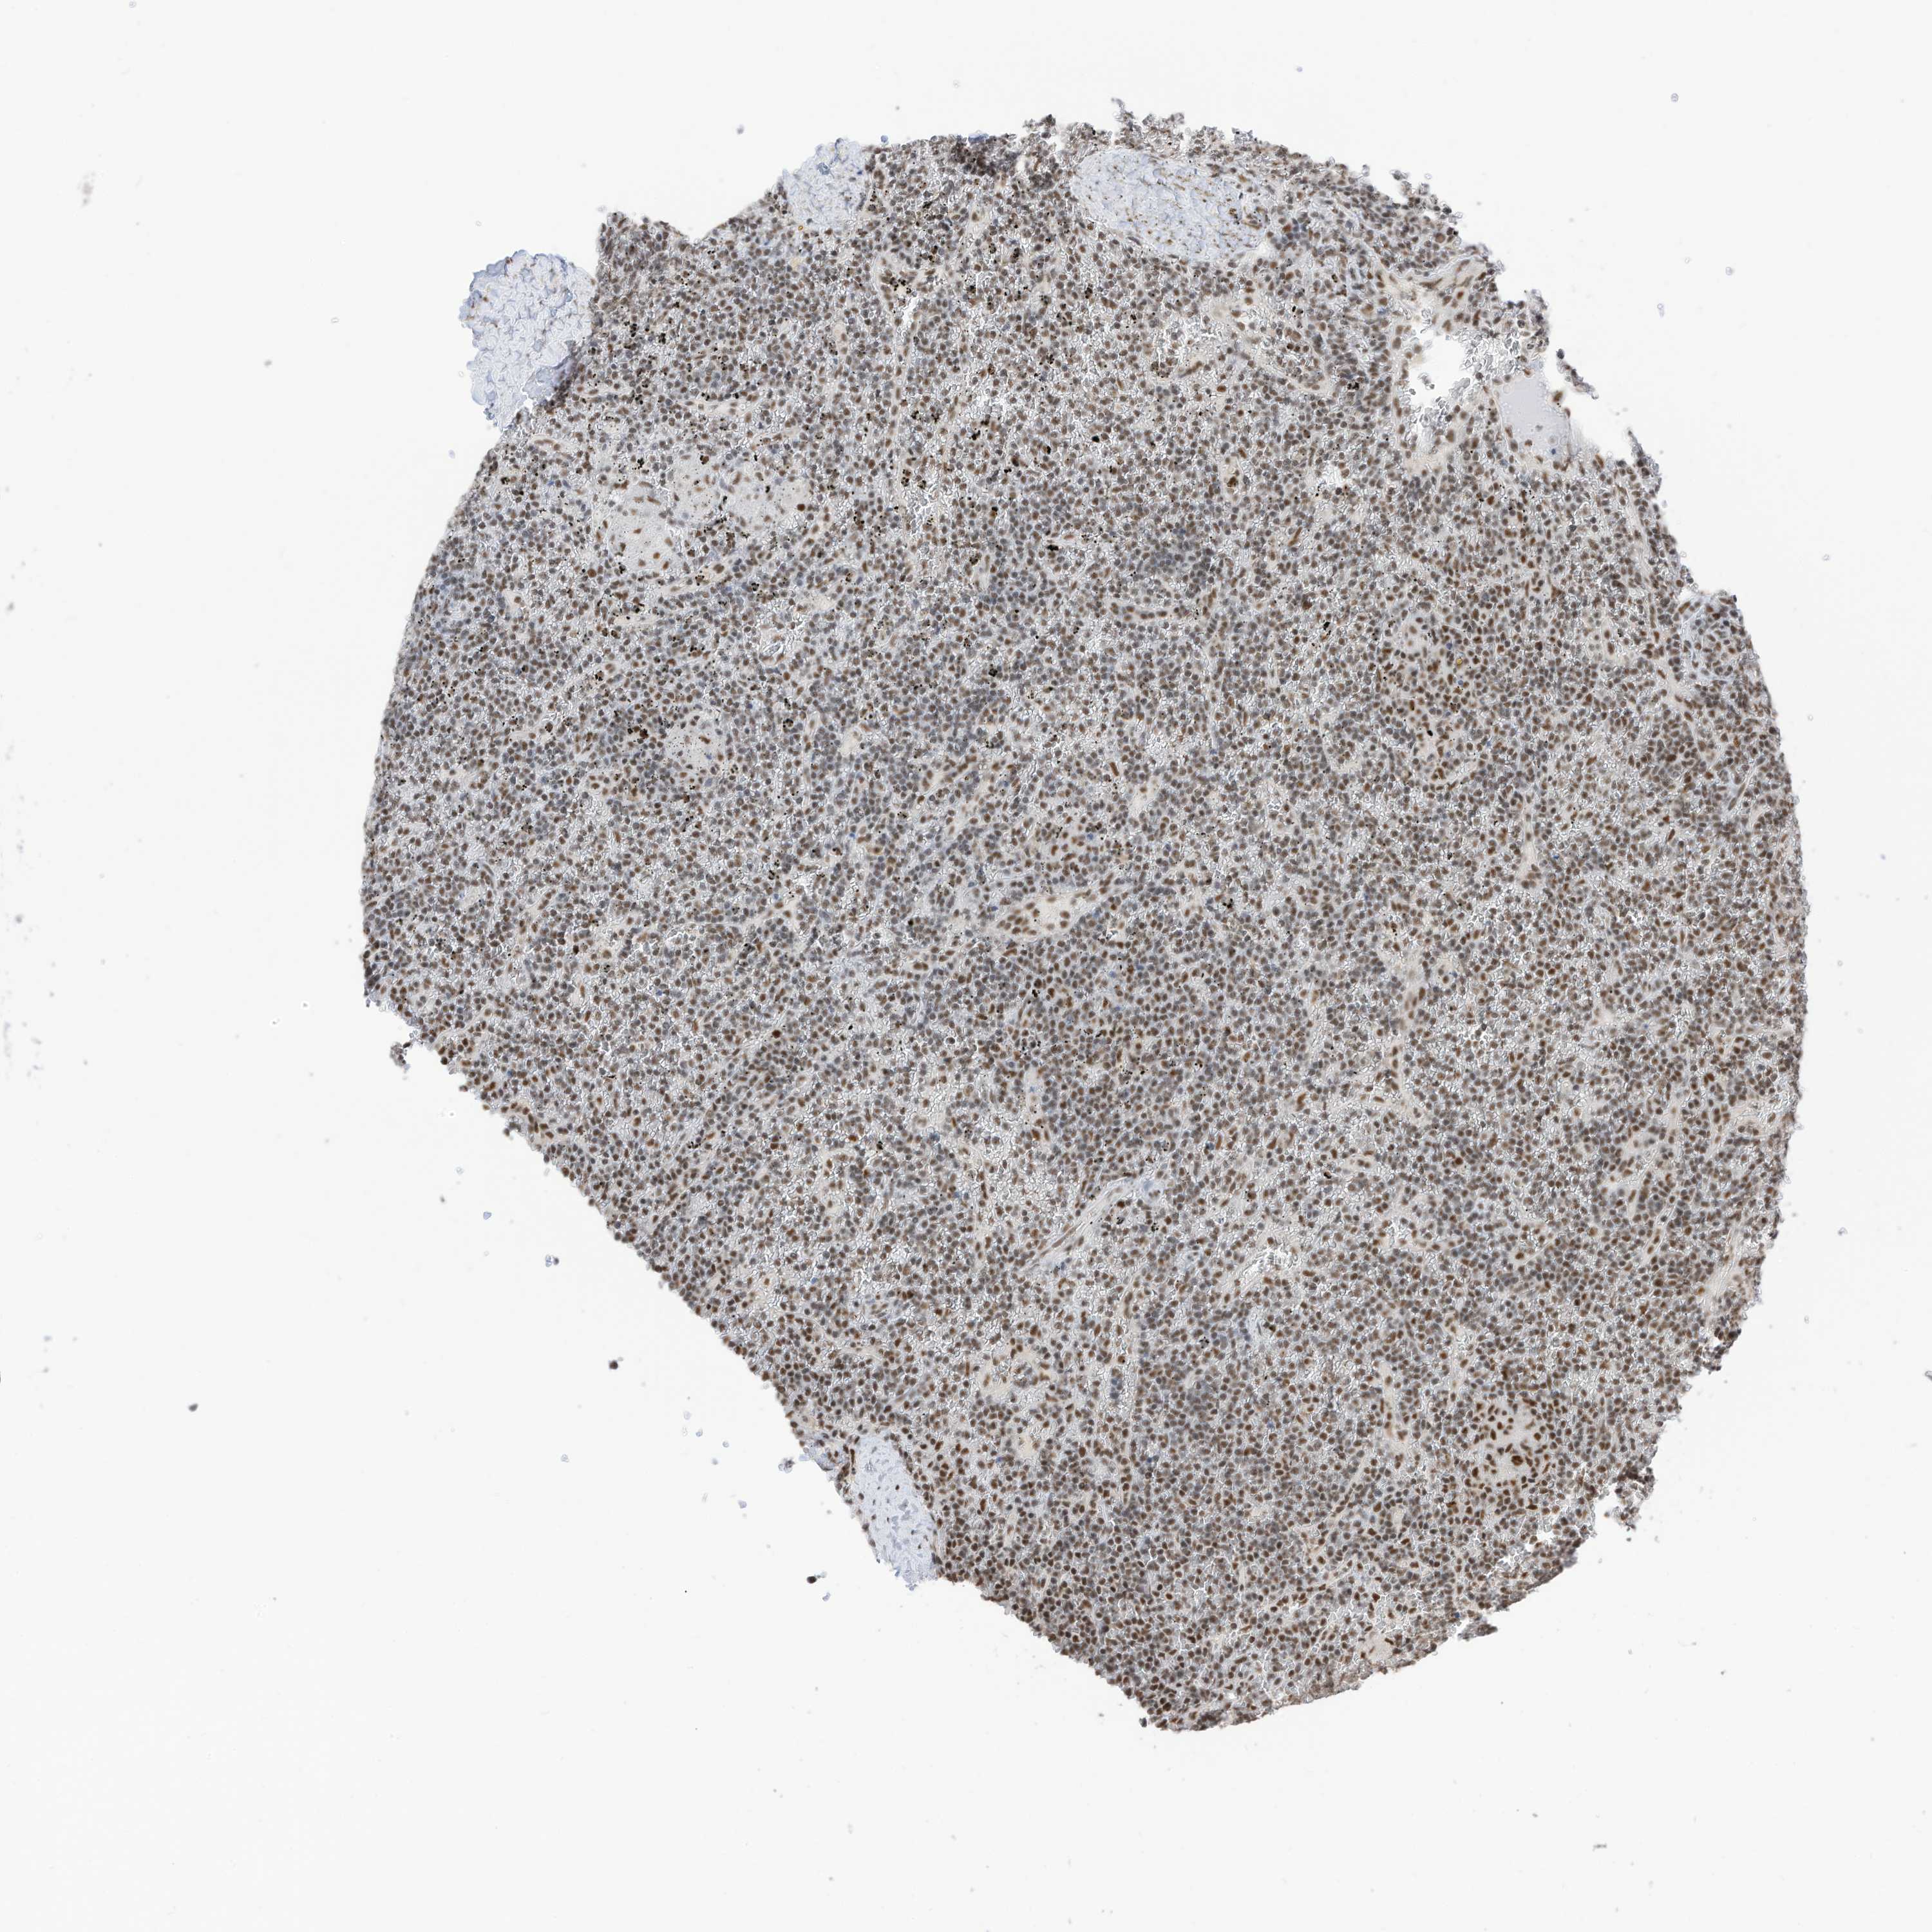

LYMPHOMA - Protein expressioni

A mouse-over function shows sample information and annotation data. Click on an image to view it in a full screen mode. Samples can be filtered based on level of antibody staining by selecting one or several of the following categories: high, medium, low and not detected. The assay and annotation is described here.

Antibody staining in the annotated cell types in the current human tissue is reported as not detected, low, medium, or high, based on conventional immunohistochemistry profiling in selected tissues. This score is based on the combination of the staining intensity and fraction of stained cells.

Each image is clickable and will lead to virtual microscopy that enables deeper exploration of all samples and also displays staining intensity scores, fraction scores and subcellular localization as well as patient and tissue information for each sample.

Antibody HPA032054

Antibody HPA032055

Staining

High

Intensity

Strong

Quantity

>75%

Location

Nuclear